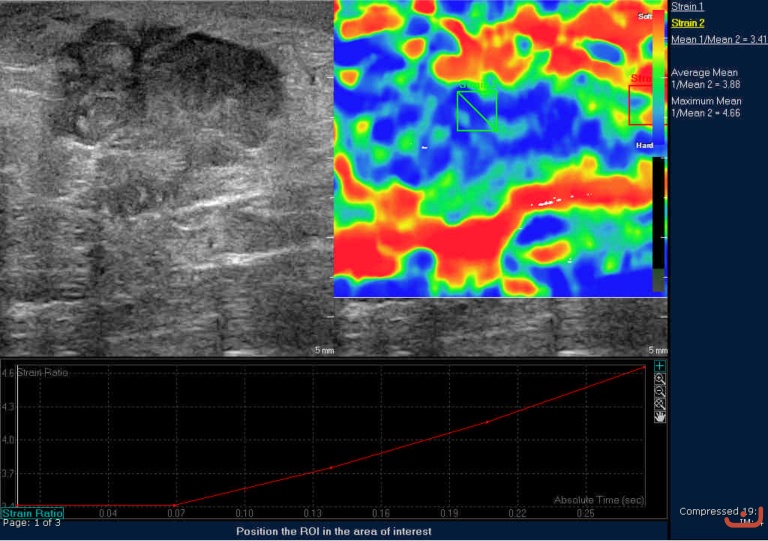

Case 44-E1

Malignant solid mass